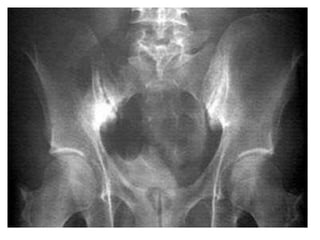

Radiographic Findings

• SacroIliac Joints-Early patchy osteoporosis

develop around the distal third of both the

bones. Joint margins become illdefined and

the joint intervals become widened.

Subchondral erosions start and when multiple

produce a rosary effect.